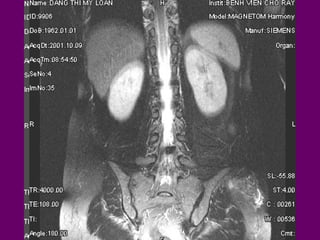

Di caên coät

soáng